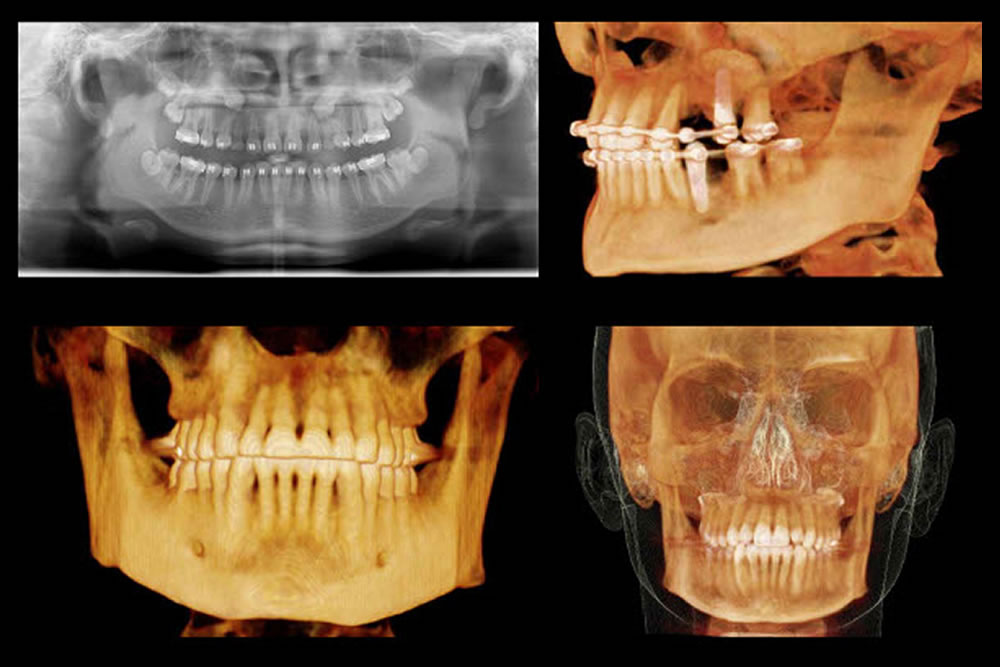

CTを駆使した精密検査

親知らずが歯茎の中に埋まっている場合や、根の形が複雑な場合には、抜歯が難しくなることがあります。当院では、必要に応じてCT撮影を行い、親知らずの状態だけでなく神経や血管の位置までしっかり確認したうえで、安心して抜歯を受けていただけるよう治療計画を立てています。